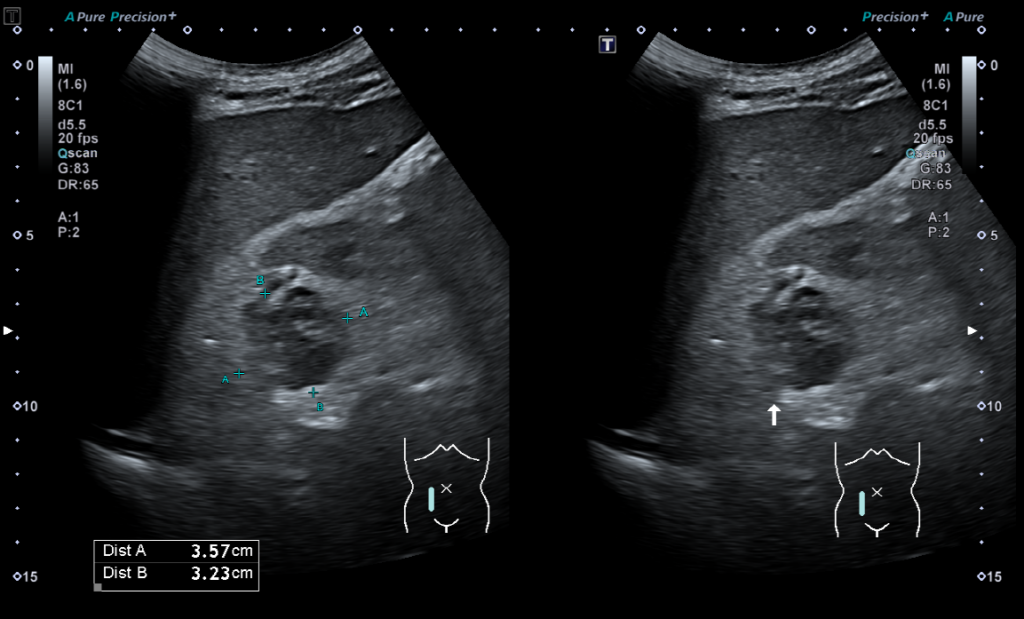

신장암 초음파 및 CT 케이스 2월 5, 2026 작성자: lupin21kr 관련 포스팅 : 췌관 확장 (Main pancreatic duct dilatation) 혈액검사에서 염소 (chloride, Cl)를 체크하는 이유 건강검진 결과지 해석 잘못된 사례 피검사로 암수치를 확인한다. 암표지자 종양표지자의 종류와 진실 8월 31일 부터 코로나 검사비용 자비로 부담해야 한다?